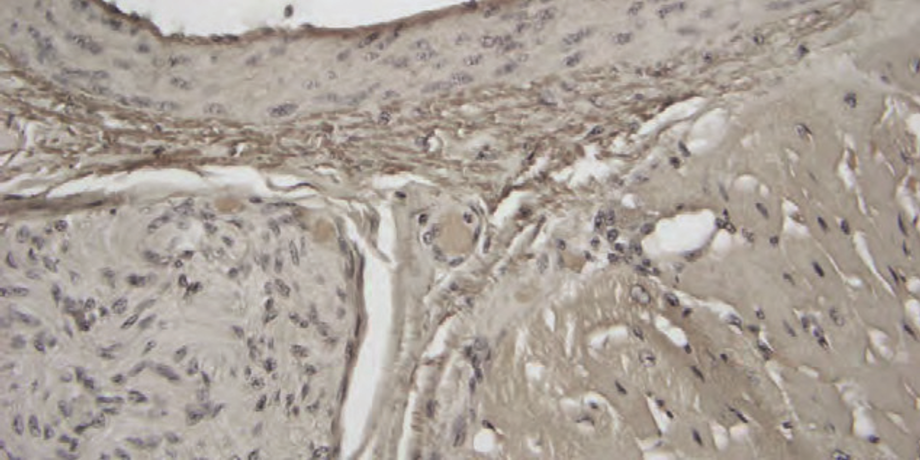

Obr: Řez ledviny v impregnačním barvení na retikulin (Gordon & Sweets). Retikulární vlákna jsou špatně impregnovaná stříbrem a na skle je v pozadí vidět precipitát. Je velmi obtížné určit příčinu podobných problémů, pokud není dodržen přesný protokol metody.